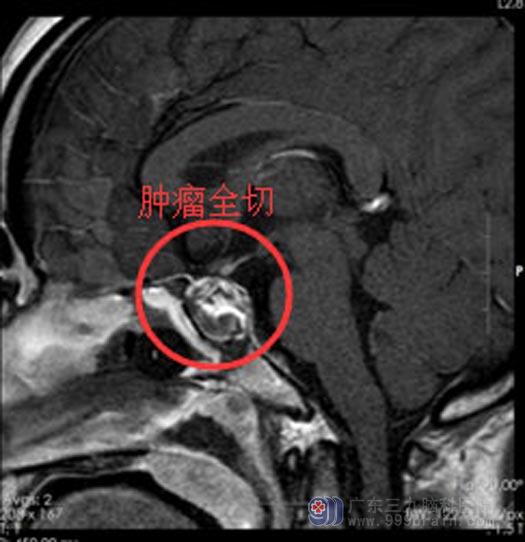

经家属同意后在内镜下经鼻碟鞍区行垂体腺瘤切除术,肿瘤顺利切除,术中对垂体、视神经、鞍底保护良好。术后无脑脊液漏、电解质紊乱等并发症,术后视力较前明显改善,泌乳素水平也渐渐恢复到正常范围。

手术后